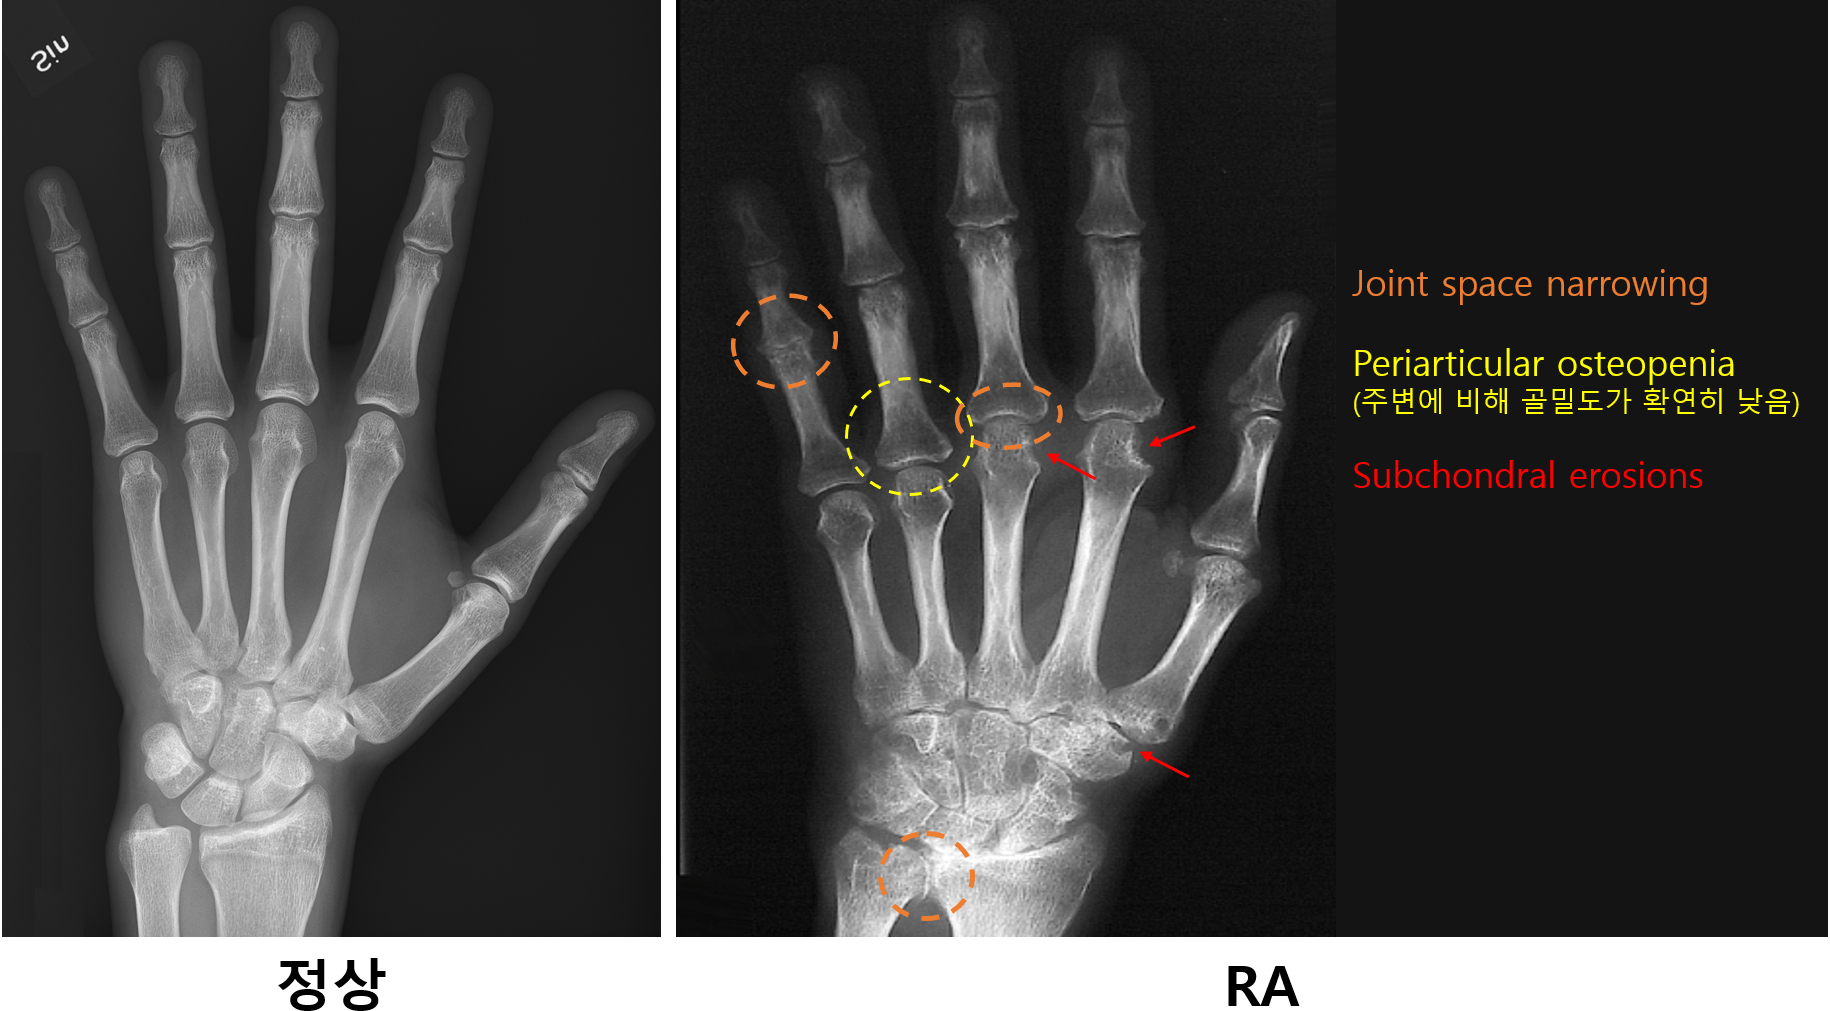

2) Plain X-ray

(1) Joint space narrowing

(2) Periarticular osteopenia

(3) Subchondral erosion, soft tissue swelling 등

검사소견 | • RF(+), anti-CCP Ab(+) • Hand X-ray: Joint space narrowing, 관절주변 osteopenia, bone erosion 등 • 관절천자: 불투명한 노란색, WBC > 2000/mm3 |